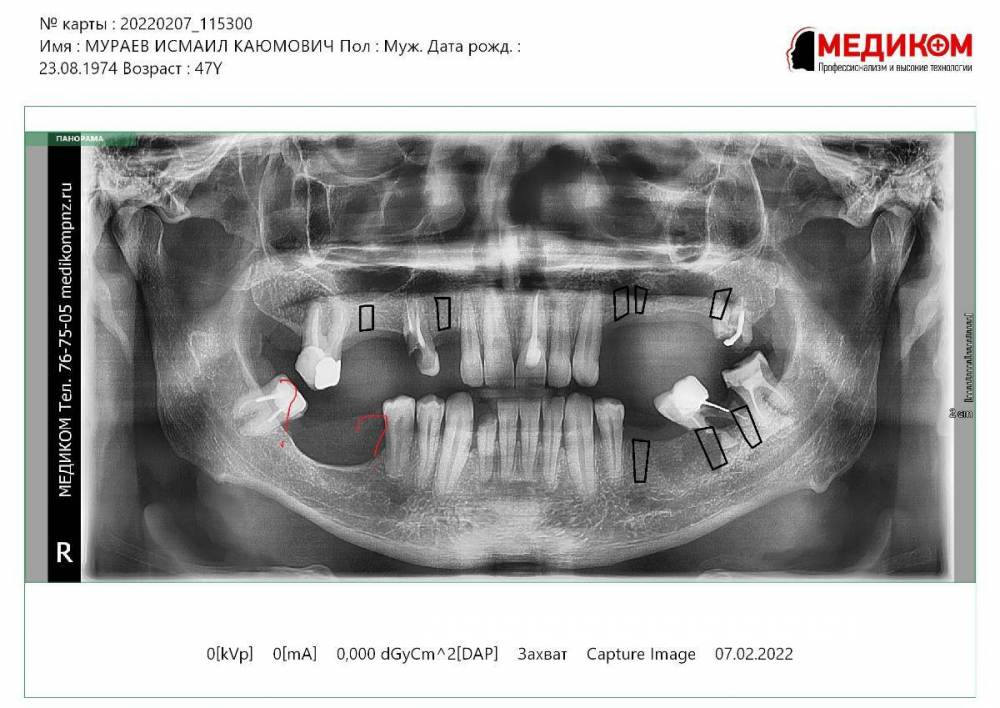

Bibars Опубликовано 16 декабря, 2023 Поделиться Опубликовано 16 декабря, 2023 (изменено) Здравствуйте. Уважаемые доктора, подскажите, пожалуйста. Пациент и. 49 л требуется полная реабилитация. 14, 27, 37, 38, 42, 48 периапикальные изменеия. Хочу сохранить 17, 42. План примерно следующий: установить импланты в области 13, 14,16 24, 25, 28, 35, 37, 38. Не уверен что делать с 4 квадрантом? в голове 2 варианта 1)Подсыпать кость 2) установить коротыши Anyridge . Если есть какие то дополнения, замечания, прошу поправьте . Если нужны еще какие то срезы ССылка на кт https://disk.yandex.ru/d/VS0gWCBpR_Mq9w Изменено 16 декабря, 2023 пользователем Bibars Ссылка на комментарий

Irouil Опубликовано 16 декабря, 2023 Поделиться Опубликовано 16 декабря, 2023 1 прячьте личные данные пациента, он Вам за это спасибо не скажет 2 если Вы всерьёз рассматриваете вариант "подсыпать кость" в таких условиях - точно не подсыпАть 3 для безопасной работы тут нужны импланты 4-4.5 мм, ЕМНИП у эниридж 5.5 мм, так что лучше рассмотреть ТЛ 4 если супракрестальной аугментацией и ТЛ имплантацией не владеете - я бы нашёл доктора, который владеет, договорился бы на референс пациента за право поприсутствовать на операции 1 4 Ссылка на комментарий

Большой Зеленый Опубликовано 19 декабря, 2023 Поделиться Опубликовано 19 декабря, 2023 Однозначно НКР . сетку, Кури, сосиску ,крышку сундука ..любой вариант которым владеете Ссылка на комментарий

Bier Опубликовано 19 декабря, 2023 Поделиться Опубликовано 19 декабря, 2023 а я бы 2 астры по 6мм нашел куда поставить 1 Ссылка на комментарий